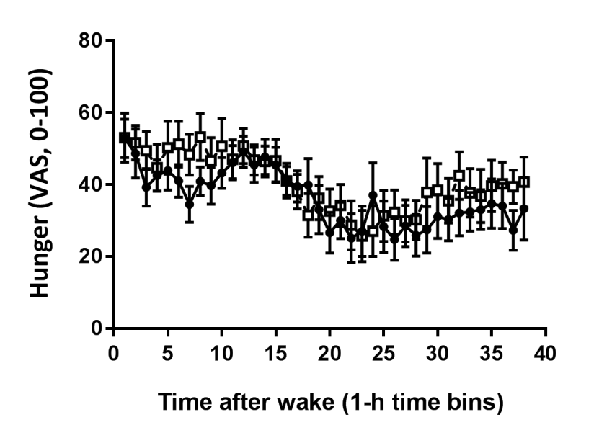

Hormonal response profiles to standardized meals are compared between normal and delayed meal timing conditions, revealing shifts in metabolic hormone rhythms.

Meal Timing Regulates the Human Circadian System.

Average plasma glucose concentration under constant routine conditions is reduced following a 5-hour delay in meal times, suggesting meal timing significantly influences glucose metabolism rhythms.

Meal Timing Regulates the Human Circadian System.